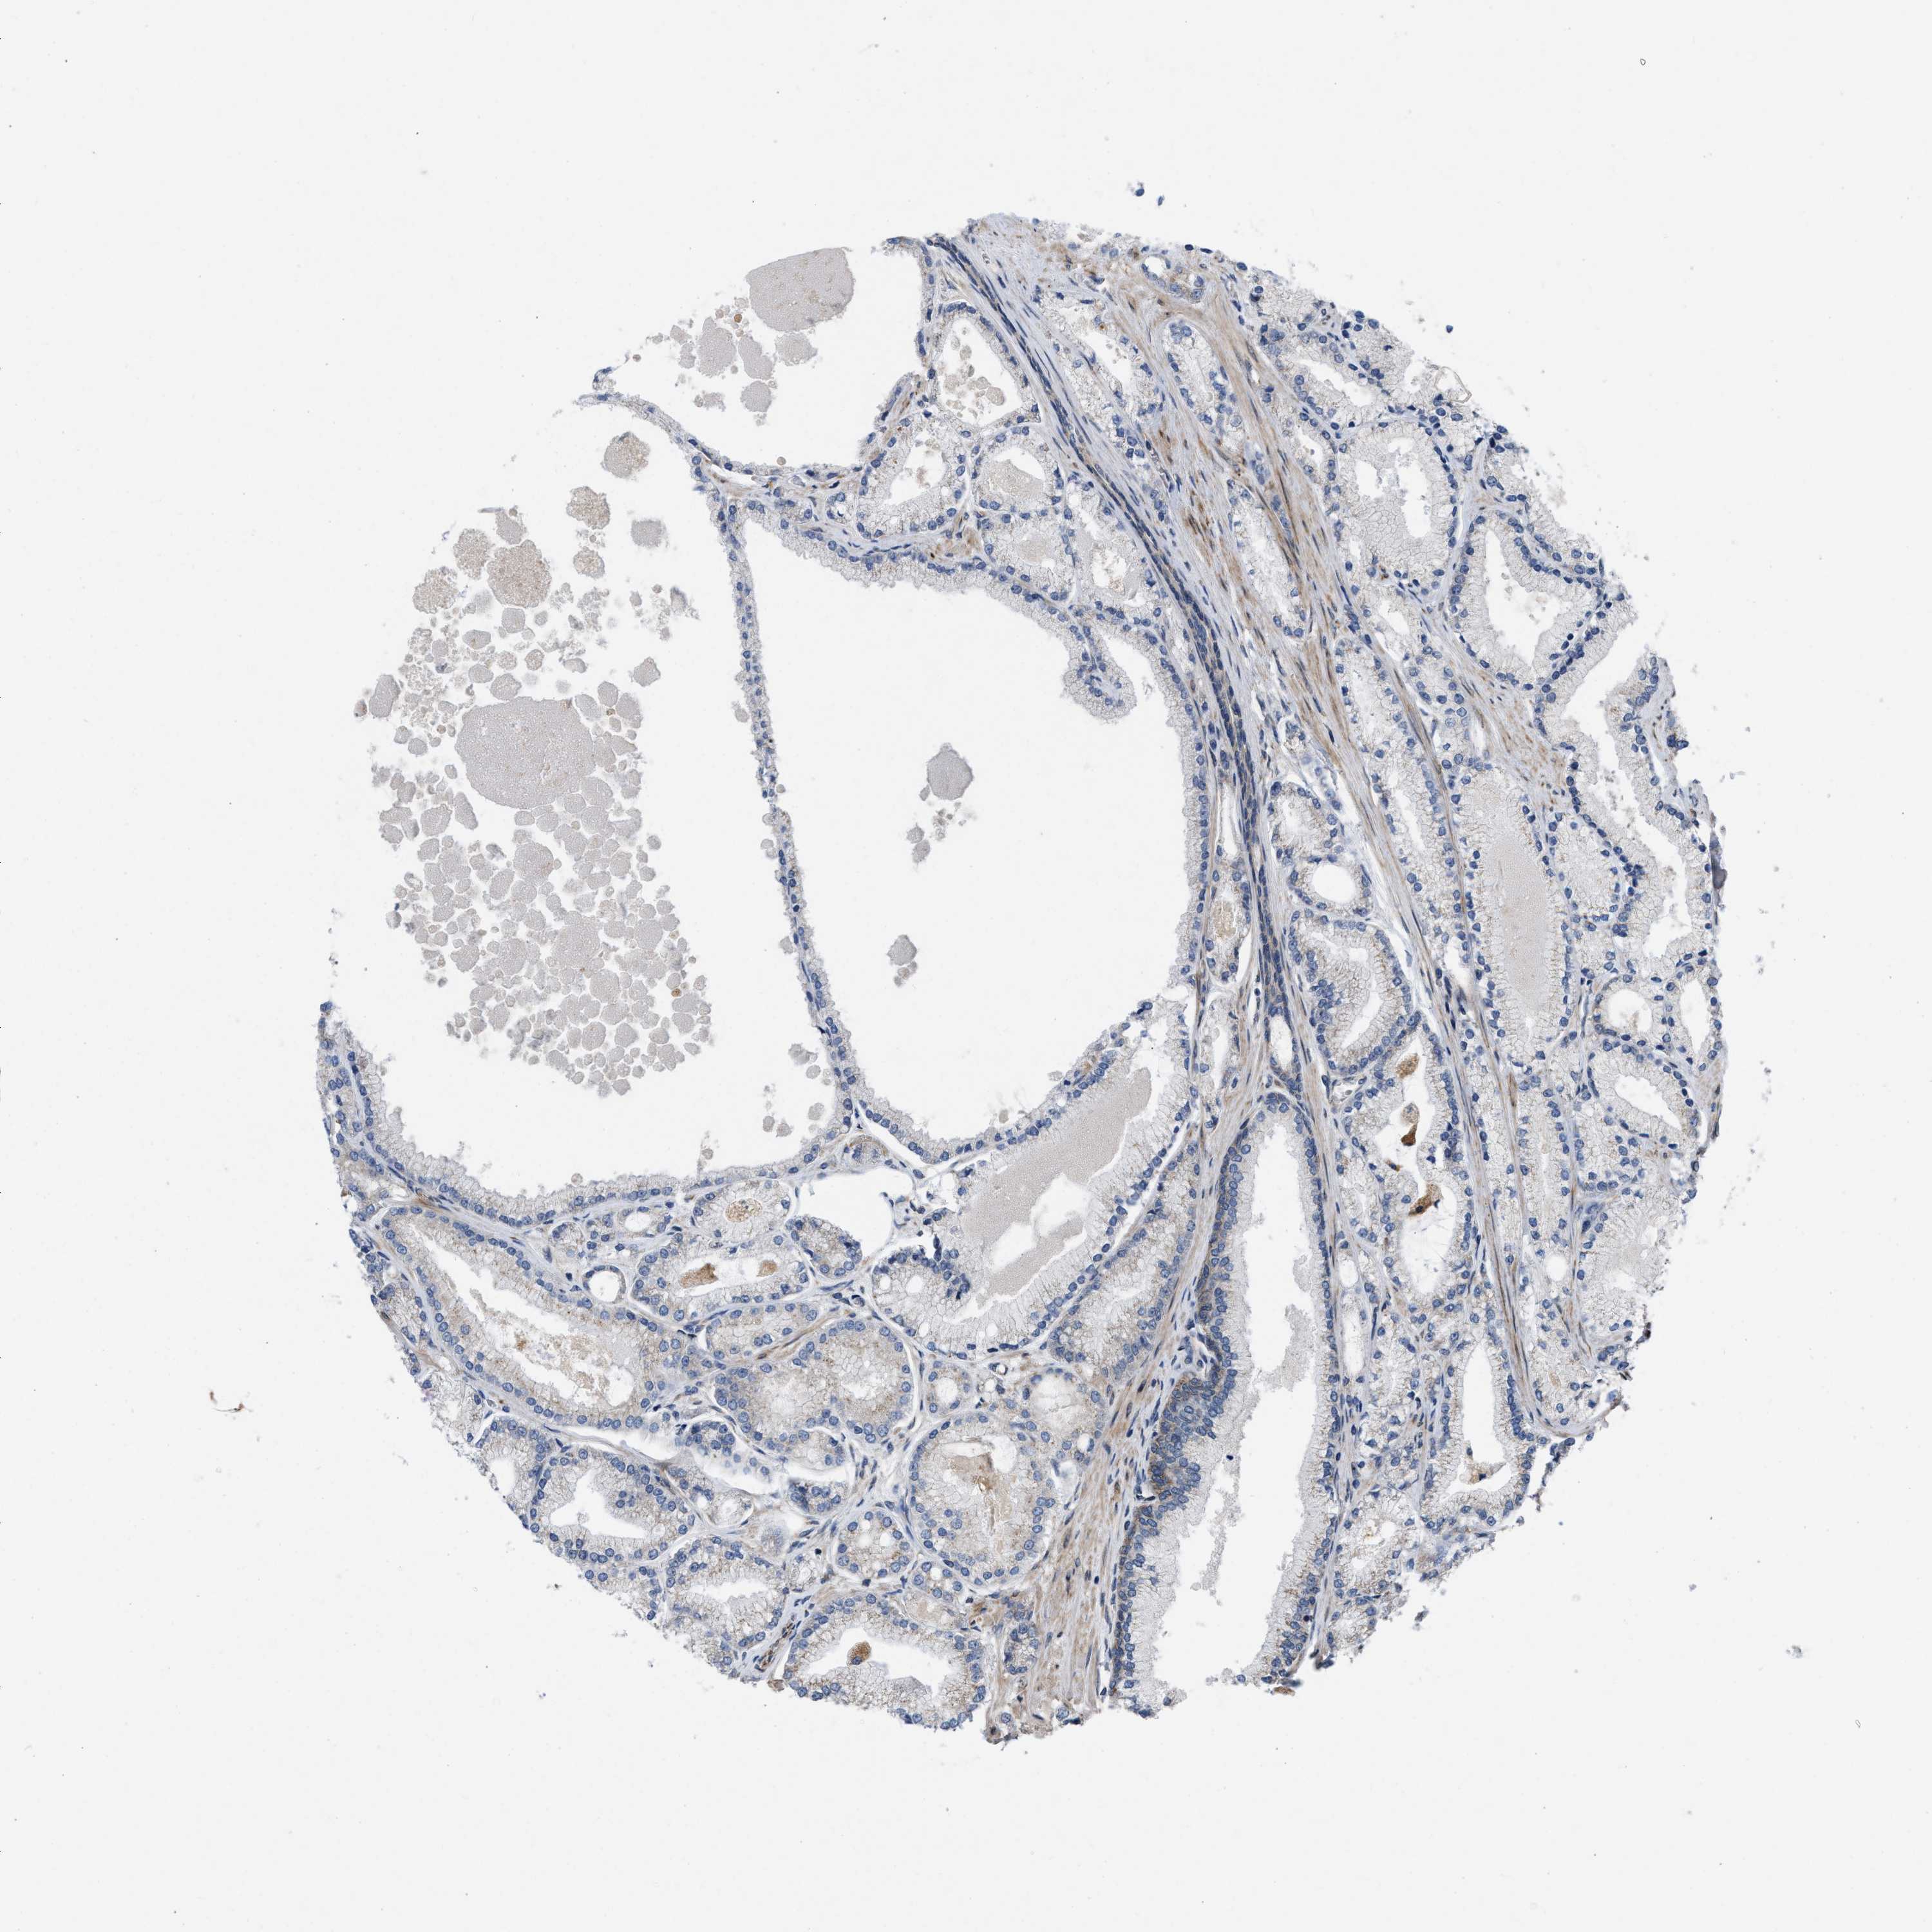

PROSTATE CANCER - Protein expressioni

A mouse-over function shows sample information and annotation data. Click on an image to view it in a full screen mode. Samples can be filtered based on level of antibody staining by selecting one or several of the following categories: high, medium, low and not detected. The assay and annotation is described here.

Note that samples used for immunohistochemistry by the Human Protein Atlas do not correspond to samples in the TCGA dataset.

Antibody stainingi

Antibody staining in the annotated cell types in the current human tissue is reported as not detected, low, medium, or high, based on conventional immunohistochemistry profiling in selected tissues. This score is based on the combination of the staining intensity and fraction of stained cells.

Each image is clickable and will lead to virtual microscopy that enables deeper exploration of all samples and also displays staining intensity scores, fraction scores and subcellular localization as well as patient and tissue information for each sample.

Antibody HPA019460

Staining

High

Medium

Low

Not detected

Intensity

Strong

Moderate

Weak

Negative

Quantity

>75%

75%-25%

<25%

None

Location

Nuclear

Cytoplasmic/membranous

Cytoplasmic/membranous,nuclear

Adenocarcinoma, High grade

Adenocarcinoma, Low grade